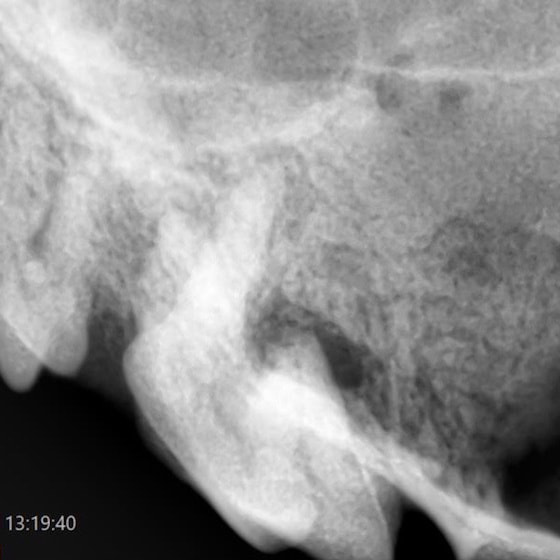

5.口腔内レントゲン検査

麻酔下で口腔内の詳細な情報を得るためレントゲン検査を行います。

口腔内レントゲン写真

撮影した口腔内のレントゲン画像腹部や胸部を撮影する一般的なレントゲンと比較して、歯とその周囲組織の鮮明な画像を得ることが可能です

プロービングと口腔内レントゲン検査の結果、左上顎第4前臼歯の根尖周囲病巣から、皮膚に波及した外歯瘻と診断しました。